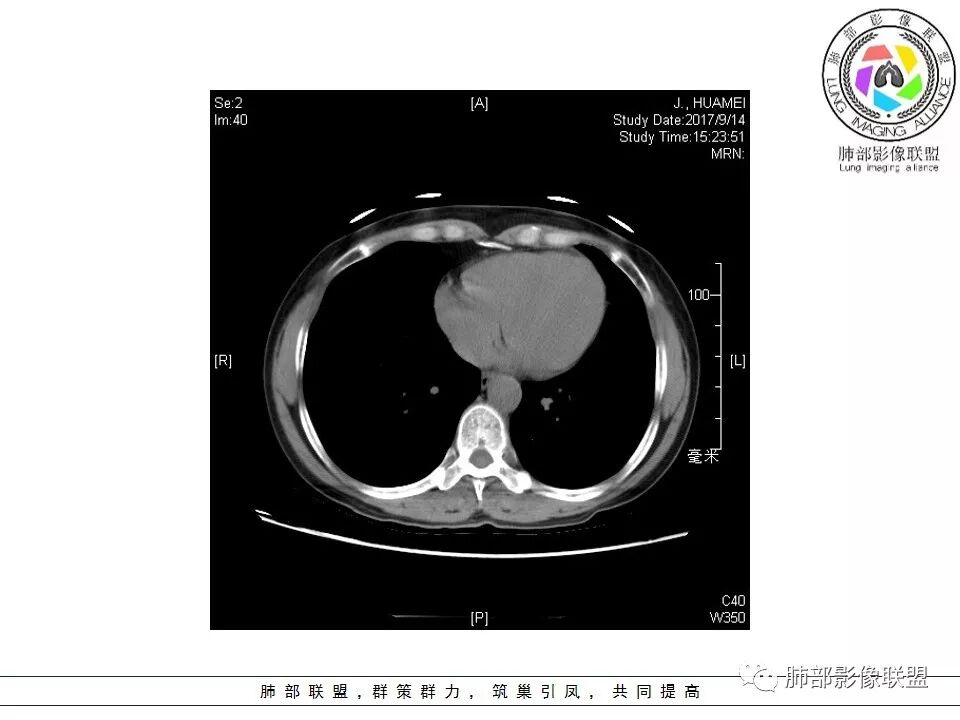

淋巴瘤与小细胞癌鉴别,纵隔内没有肿大淋巴结、结节边缘比较毛糙,淋巴瘤放第一位。

恶性的血管穿行自然,包括支气管稍扩张,最常见还是淋巴瘤,它强化比较均匀;

原发性肺淋巴瘤(PPL)是指肺实质或支气管的淋巴组织异常增生,侵犯的主要对象就是肺间质和支气管粘膜下组织,无纵膈、肺门及其他部位的淋巴瘤,在发病时或者确诊后3个月内没有肺外病变的证据,是结外肺淋巴瘤的一种罕见类型,而PPL最常见的就是结外边缘区黏膜相关淋巴瘤组织(MALT)淋巴瘤,其次是弥漫大B细胞淋巴瘤。

肺内黏膜相关淋巴组织淋巴瘤(MALT)

MALT淋巴瘤为低度恶性肿瘤,是肺内原发性淋巴瘤中最常见的类型,其部分征象与其他肺内恶性淋巴瘤表现不一样;因为MALT淋巴瘤生长缓慢,对缺氧耐受好,病灶中罕见坏死。很少引起胸内淋巴结,肺门及纵膈内淋巴结一般不肿大。胸膜及叶间裂轻度累及或不累及,胸膜增厚少见,胸膜外脂肪间隙清晰,即使累及胸膜,引起胸腔积液也少见,如有胸腔积液也多为良性,与淋巴管或静脉阻塞有关,也可能为病变靠近胸膜而发生的反应性渗出。肺MALT淋巴瘤具有一定的散播性,就诊时40%以上的病人存在肺外器官受累,最常见的肺外器官受累是胃。

病例小结:如临床症状轻,肺内多发或单发的结节、肿块及实变,沿血管支气管束、肺间质及胸膜下分布,密度及强化均匀,伴支气管充气征,支气管可扩张,血管造影征,周围有间质性改变,有炎性特点(平直、收缩、周围晕征及树芽),又有肿瘤特点,纵膈及肺门未见肿大淋巴结,没有明显胸膜增厚及胸腔积液,尤其是影像相对稳定,都要想到这个肺黏膜相关淋巴组织淋巴瘤的可能;回顾性分析本病例,还是很符合MALT淋巴瘤影像表现;但是这个患者的NSE轻度升高,使很多群友都想到了小细胞肺癌、类癌的这些神经内分泌肿瘤;神经元特异性烯醇(NSE),是小细胞肺癌、类癌还有其他神经内分泌肿瘤的特异性和敏感性较高的肿瘤标志物,正常值为0-16ng/ml,但是此患者NSE值为17.1ng/ml,为轻度升高;如果在小细胞肿瘤和神经内分泌肿瘤中,NSE是成数十倍的增高,恶性肿瘤的可能性就比较大。如果是轻度升高,诊断神经内分泌肿瘤意义不大,而且里面的支气管充气征伴扩张都不大符合小细胞肺癌和类癌的影像表现。小细胞癌常进展迅速,转移早。